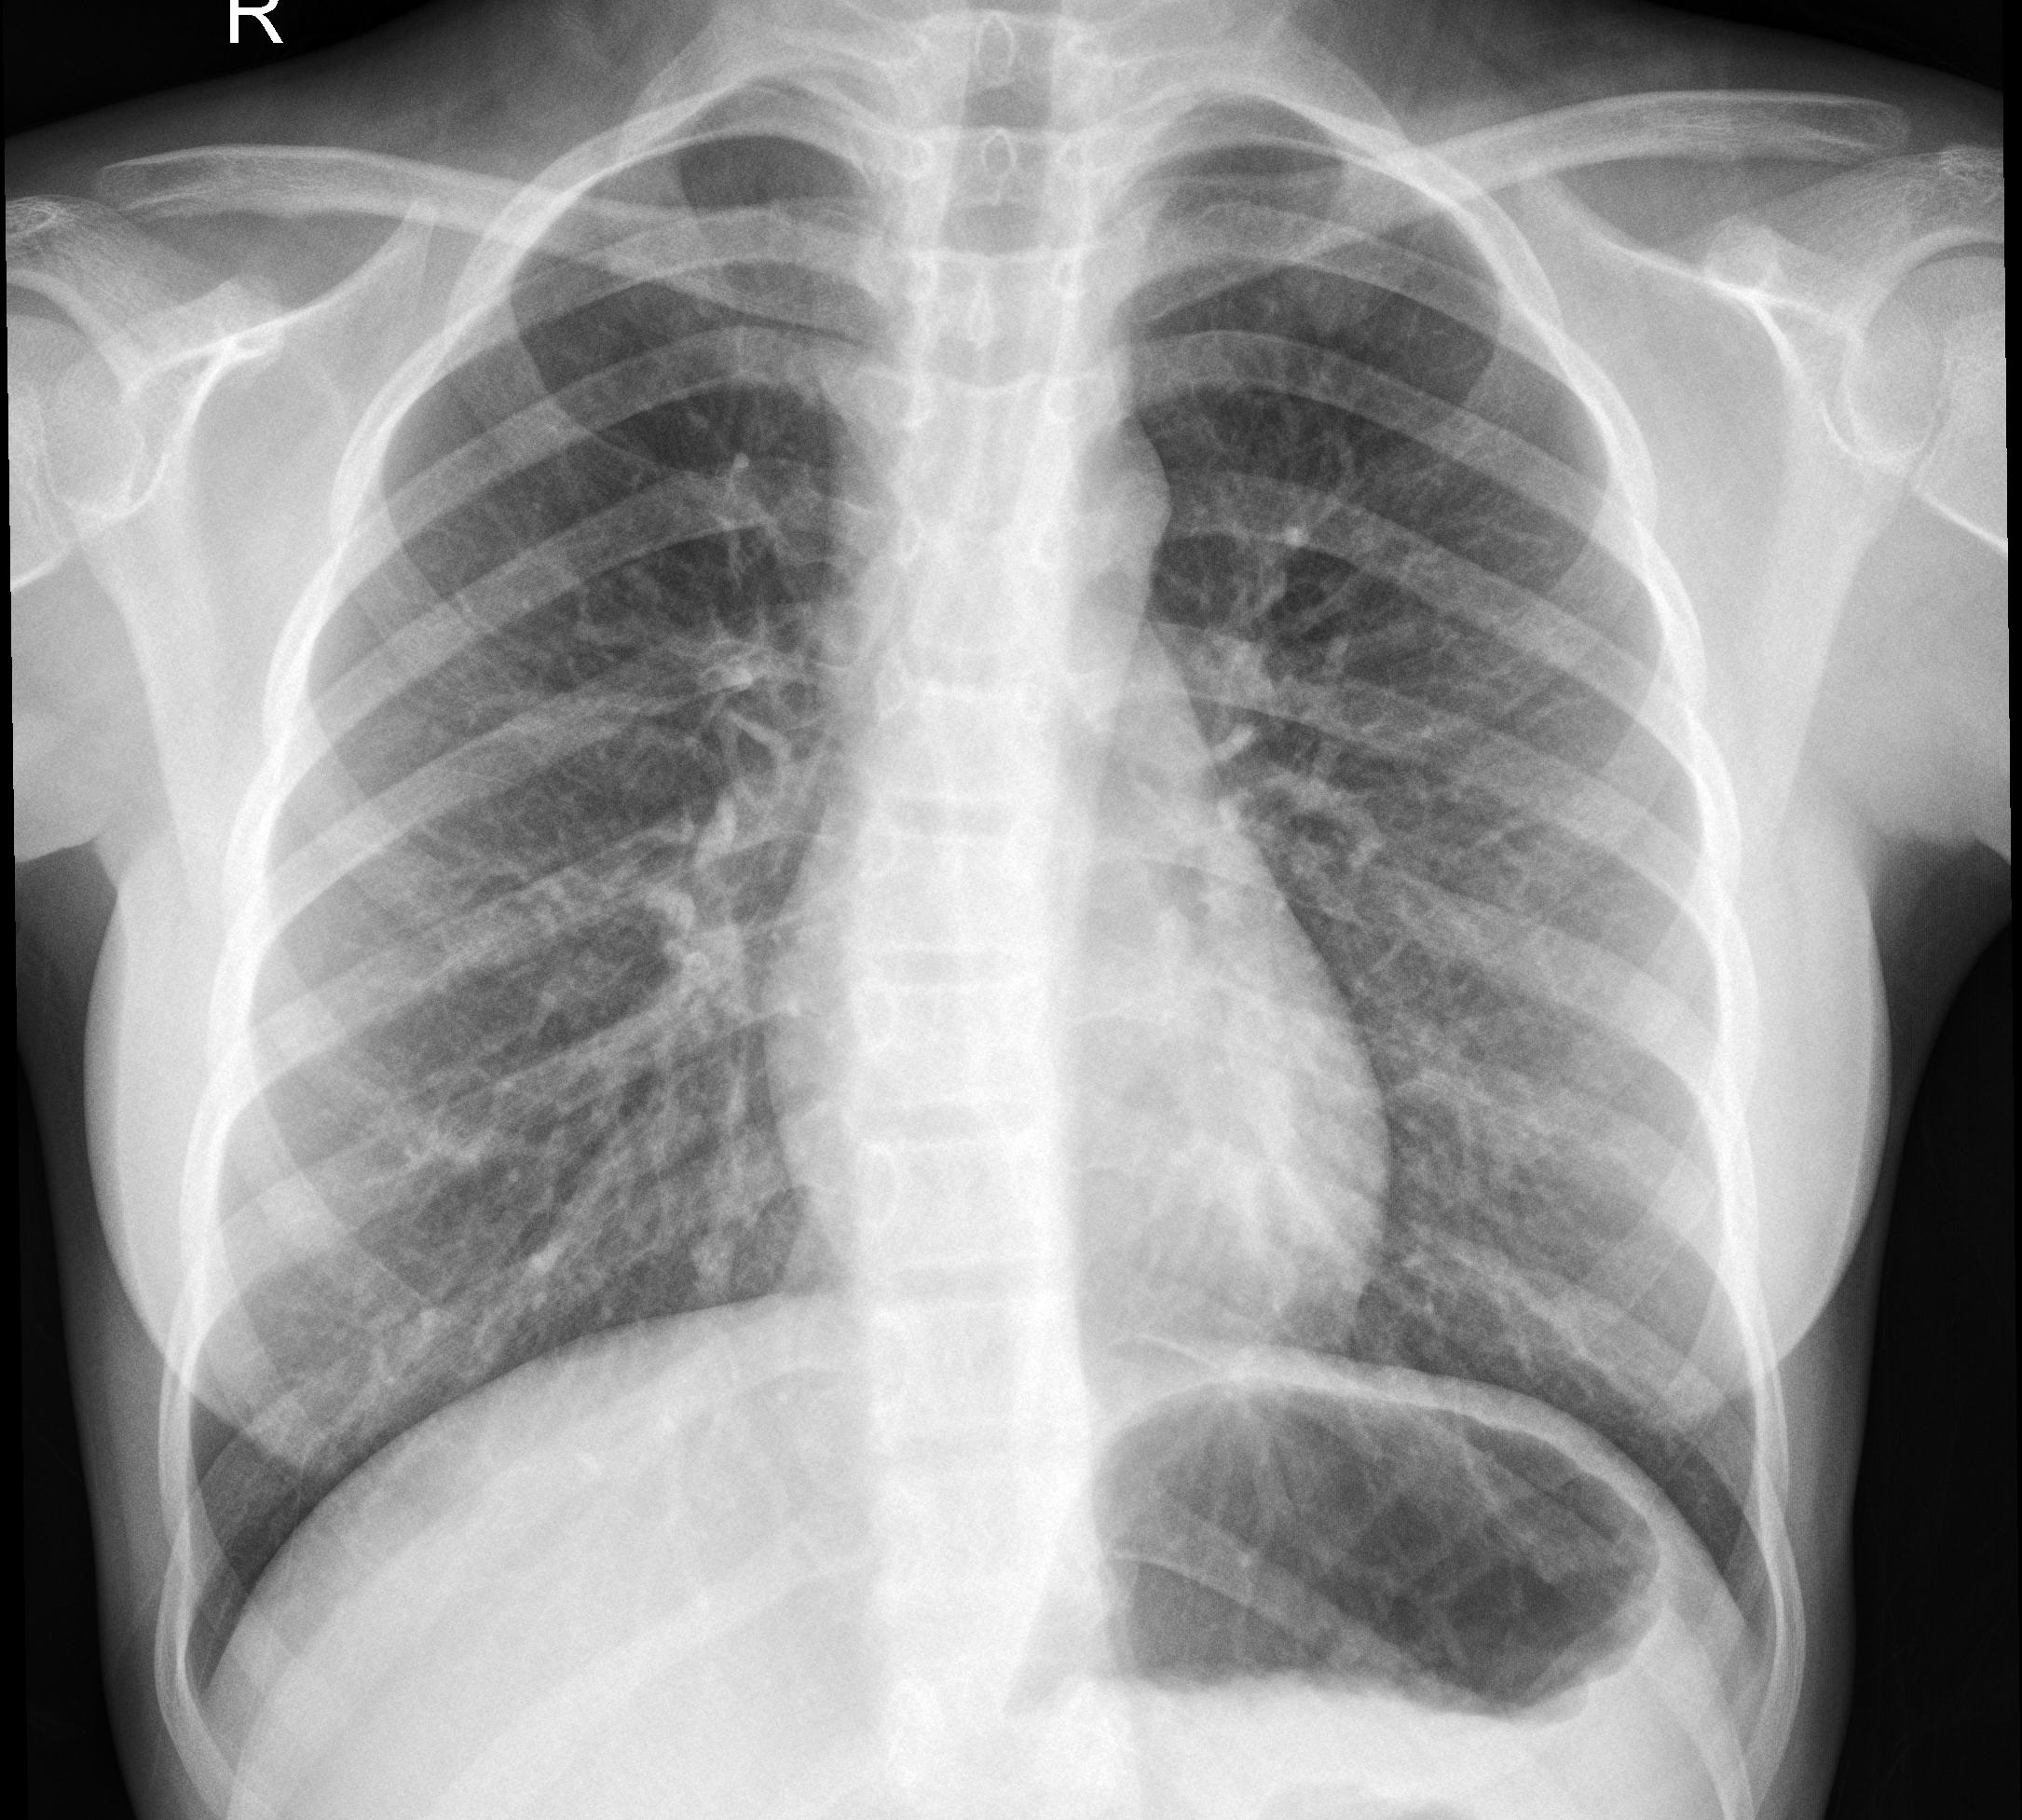

The spread of coronavirus disease progressed so quickly that it did not keep up with diagnosing in hospitals, which is why the rapid production of the RT-PCR test kits became very important, which also caused some problems with accuracy and the unreliability of some of them. The main symptoms are breathing difficulties and high fever. Studies have shown that in the early stages of the disease, chest X-rays provide a more accurate result than the PCR method. For this purpose, we have created an online system that recognizes CoVID-19 by analyzing the x-rays.